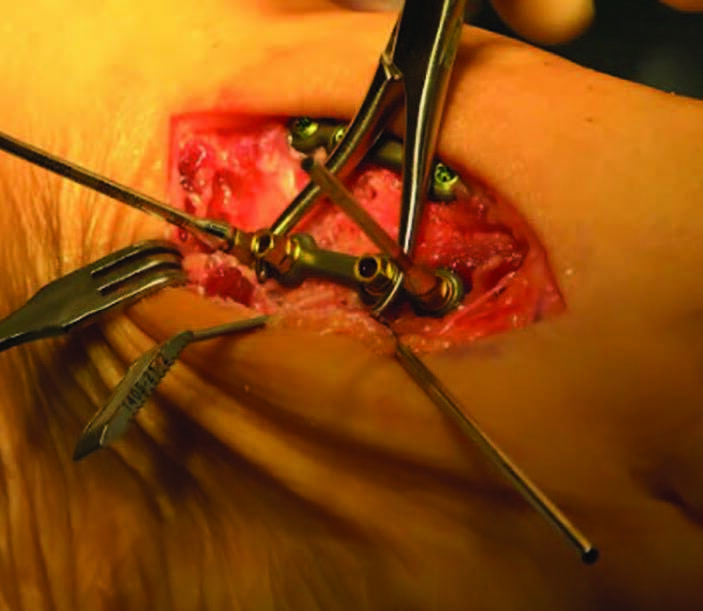

The cut guide keel for this technique interfaces with the second and third TMT, and the cut slots align over the joint spaces in their respective planes. The cannulated outrigger fixation points provide a fluoroscopic visual reference to ensure there is no parallax when determining the guide position at the osseous anatomy. The medial aspect of the cut guide lines up at the lateral border of the medial cuneiform. The surgeon checks the lateral border of the cut guide with C-arm, and inserts a metal marker or fulcrum between the third and fourth metatarsals to delineate the far border of the third metatarsal. These steps and checks reduce the risk of saw blade injury to the medial cuneiform and fourth metatarsal. The goal of the cut guide anatomy is to allow for creation of a continuous angular bone cut at both the metatarsal and cuneiform joint surfaces. This exposes the subchondral bone surfaces to promote arthrodesis similar to the Lapiplasty® (Treace Medical Concepts, Inc.) instrumented triplanar approach at the first TMT.29

Autologous cancellous bone graft may augment arthrodesis in this region. Liberal fenestration of the surfaces facilitates localized bone graft incorporation and helps the joint surfaces interdigitate during bone docking, in my experience. An “up and out – gate-hinge closure” technique reduces the midfoot deformity and the bone gap created by the cuts.1 One performs this technique manually, or assisted with a compressor device, which further stabilizes the reduction and acts as a form of provisional fixation at the lesser TMTs. One applies this device across the third TMT, and fixation is with two parallel threaded olive wires from the lateral aspects of the second and third metatarsals to the medial and intermediate cuneiforms, respectively. The fourth and fifth metatarsals have flexibility at their respective metatarsocuboid joints, which allows for motion back into position without the need to perform an osteotomy or arthrodesis of the lateral column.

The surgeon places fixed-angle locking plates and screws across the normal anatomic contours of the second and third TMTs, and the plates rest on the midline of the bones. This natural angled position, oriented from lateral to medial, assures the screws enter the center of each bone. Maintaining ligamentous attachments further stabilizes the hardware. The surgeon can then reduce the first ray, with the TMT prepared similarly to maintain correction through realignment arthrodesis.30 Complete correction of the true intermetatarsal angle is made possible through initial correction of the lesser ray position and midfoot deformity. This results in reduction of foot width and predictable improvement in the radiographic angular relationships of the medial column.31,32